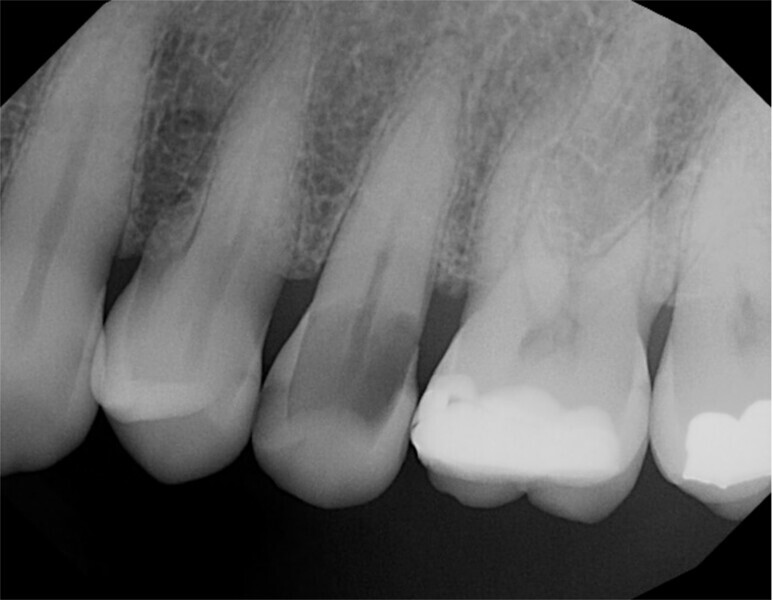

A 57-year-old male patient presented with the complaint of sensitivity to temperature in the maxillary left quadrant. A radiograph was taken (Fig. 2), and deep caries was noted in the second premolar with possible pulpal involvement. Periapical pathology was not noted radiographically. The tooth was tested with cold to verify that the pulp was vital. A mild reaction was noted when cold was applied that immediately resolved when cold was removed from the tooth, indicating that the tooth was vital. The patient was advised that endodontic treatment may be required if a large pulpal exposure resulted from caries removal or if the tooth became symptomatic after treatment. Should a small pulpal exposure be noted or caries removal result in thin dentine over the pulp, laser treatment would be utilised prior to core placement to sterilise the area and avoid pulpal infection developing. A core build-up and complete crown were planned for the tooth. The patient accepted the treatment recommendations.

Local anaesthetic was infiltrated into the buccal vestibule adjacent to the tooth to be treated. Carbide and diamond burs were utilised in a high-speed handpiece with water to access and remove the caries, leaving a layer over the pulp (Fig. 3). A #4 round bur in a slow-speed handpiece was then utilised to remove the remaining affected leathery dentine until sound tooth structure remained (Fig. 4). A small spot of affected leathery dentine over the pulp was removed last, resulting in a small pulpal exposure (Fig. 5).